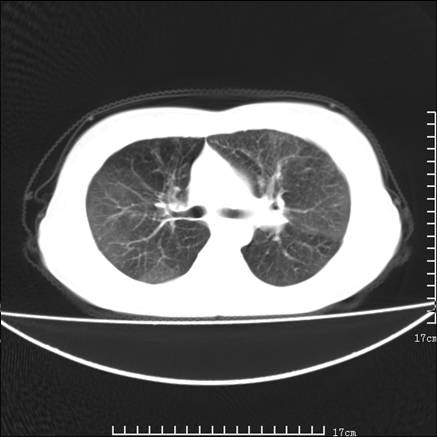

女,46岁,患胃溃疡多年,溃疡大小约1.0cm左右,后于5年前手术,病理为胃癌。主诉:半月前感冒后胸闷,气短,有咳嗽,无明显咳痰,无发热。偶有腰背部不适。

以下为高分辨扫描图像

双肺小叶间增厚,双肺散布粟米影和磨玻璃状影,以双肺上叶为重。结合病史考虑转移(癌性淋巴细管炎)可能性大。

结合病史:认为是典型肺部癌性淋巴管炎、淋巴结转移。请看图解。

正如caihe主任所言,影像表现结合临床病史应该支持肺癌性淋巴管炎;上肺大片边缘不清的渗出病变,多系感染所致,临床有感冒病史并咳嗽表现。肺癌性淋巴管炎临床一般无咳嗽、咳痰症状。

肺癌性淋巴管炎征象分为主要征象及合并征象,主要征象包括:

1、近肺门支气管血管周围间质结节状增厚;

2、小叶间隔结节状增厚;

3、小叶中央间质结节状增厚;

4、胸膜下间质结节状增厚。

合并征象为:纵隔淋巴结增大,胸腔积液,肺多发随机分布的小结节等。